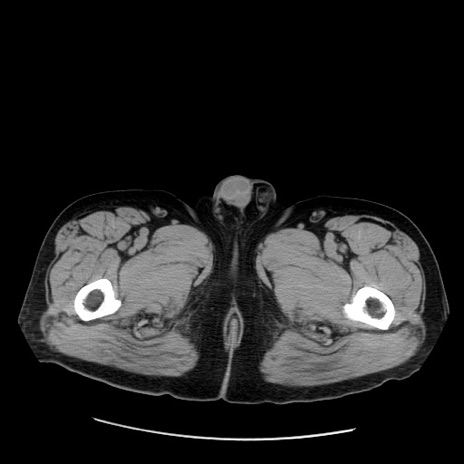

症例20(横断像)

【症例】 60歳代男性

【主訴】 腹部膨満、嘔吐

【現病歴】5日前頃より倦怠感を認め食事量減少し4日前の朝嘔吐、食事摂取困難となった。 3日前近医受診し点滴施行され整腸剤などを処方された。 当日他院を受診し、腹部膨満著明、炎症反応の上昇(CRP10.8、WBC11200)あり、紹介受診となる。

【身体所見】 意識JCS1 受け答えがはっきりしないBP 111/57mHg、 P 67bpm、、BT35.2°C、SpO2 97%(RA)、 腹部:膨隆、打診で鼓音あり、全体的に圧痛有り、腸蠕動音(-)、反跳痛ははっきりせず。

【データ】WBC 11400、CRP 14.20